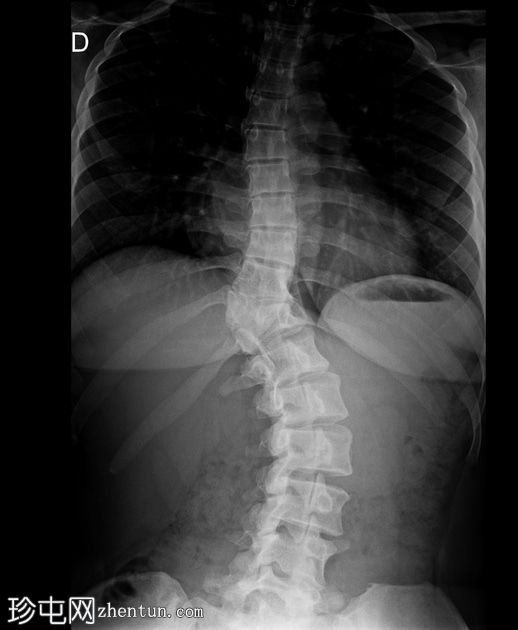

X线片

正位片

胸腰段交界处可见先天性脊柱侧弯,右侧凸出明显。

胸腰段交界处可见右侧完全节段性半椎体。

腰椎严重旋转。